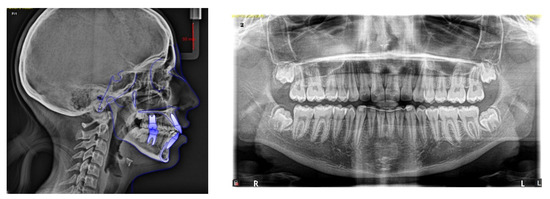

4.1. Etiology and Diagnosis

4.2. Treatment Objectives

4.3. Treatment Strategy

4.4. Treatment Progress